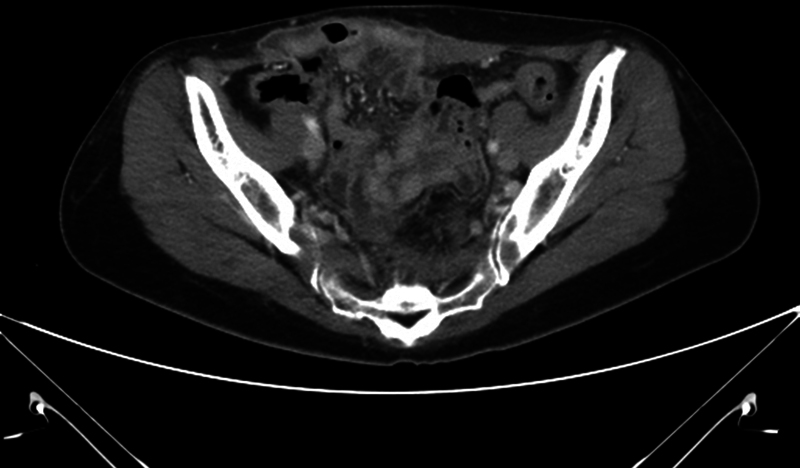

尽管许多研究报告了高强度聚焦超声(HIFU)疗法的安全性和有效性,但人们仍然担心内脏损伤。然而,关于 HIFU 治疗后腹壁疝的报道却很少见。我们报告了三例子宫腺肌症或子宫肌瘤患者在接受 HIFU 治疗后出现腹壁疝但无皮肤损伤的病例。由于症状模糊、临床怀疑不充分以及未及时进行适当的影像检查,诊断往往被延误。应将腹壁疝视为 HIFU 治疗后可能出现的并发症,当患者出现异常腹部肿胀和/或疼痛,且持续时间超过术后数月时,就应怀疑腹壁疝。

Although many studies reported the safety and efficacy of high-intensity focused ultrasound (HIFU) therapy, there are still worries about internal organ injury. However, reports of abdominal wall hernias after HIFU therapy are rare. We present three cases of abdominal wall hernias without skin injury after HIFU therapy in uterine adenomyosis or fibroids. The diagnosis was often delayed because of vague symptoms, inadequate clinical suspicion, and delayed proper image studies. Abdominal wall hernia should be recognized as a possible complication after HIFU and be suspected when the patient presents with unordinary abdominal swelling and/or pain that lasts for more than a few months after the procedure.